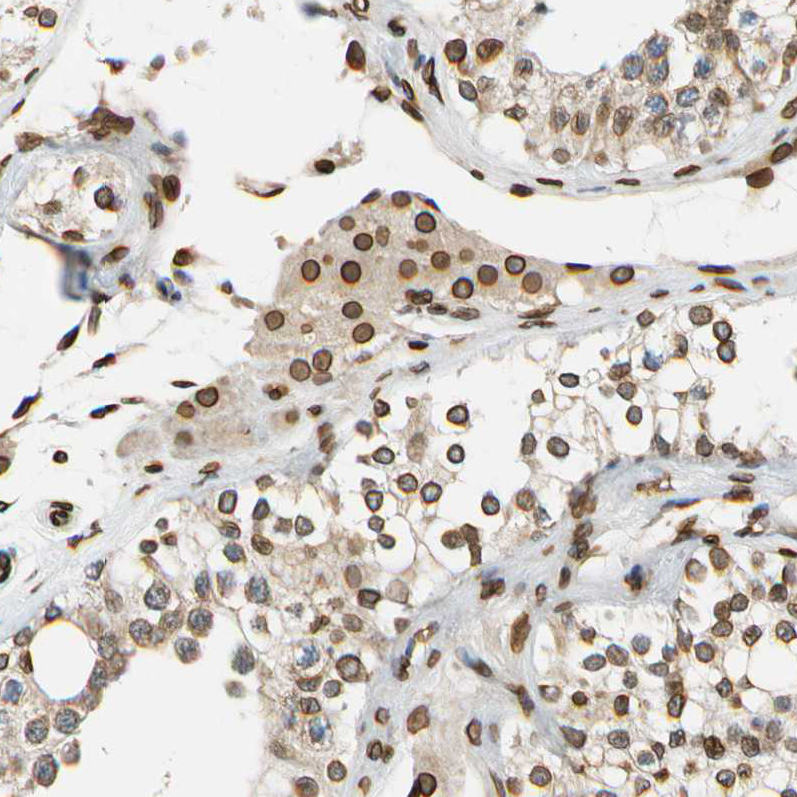

Immunohistochemistry analysis in human skin and bone marrow tissues using HPA008461 antibody. Corresponding SUN1 RNA-seq data are presented for the same tissues.